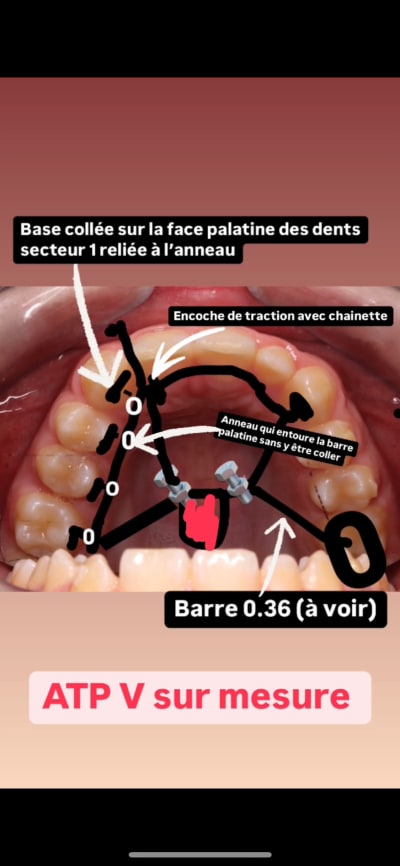

Solution Bonus – ATP-V modifié

Une base squelettique en 0.36, à vérifier pour s’assurer qu’elle est suffisamment rigide.

La face palatine des dents du secteur 1 est collée. Il s’agit de bases reliées à un anneau sur la barre palatine, avec des chaînettes permettant de tracter les dents une à une.

Un prolongement est ajouté à l’arrière des incisives maxillaires, ainsi qu’un autre partant de la face distale de la 11 jusqu’au niveau vestibulaire. Ce dispositif vise à limiter les mouvements parasites. Étant donné que les dents 13/14/15 et 16 ne seront pas directement prises en charge dans l’Ac, mais uniquement tractées par l’ATP-V, ces mouvements parasites resteront présents, bien que réduits à un taux tres faibles par rapport à tous les systèmes grâce notre traction direct sur l’ATP-V et sans prise en charge dans l’Ac des dents tractées.

Certes, cet appareil sur mesure représente un coût légèrement supérieur, mais il permet un gain de temps au fauteuil en ne nécessitant que le changement des chaînettes. De plus, il assure une efficacité accrue, permettant ainsi de se concentrer sur d’autres aspects du traitement.

Un arc transpalatin (ATP), c'est bien mais... ça bloque la molaire qu'on aimerait voir se mésialer également, ne crois-tu pas ?